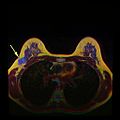

MRI showing breast cancer